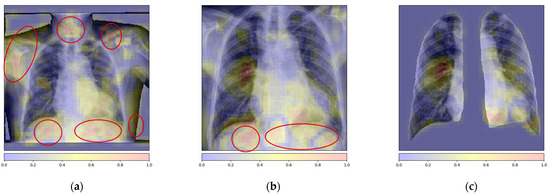

The recent Coronavirus Disease 2019 (COVID-19) pandemic has put a tremendous burden on global health systems. Medical practitioners are under great pressure for reliable screening of suspected cases employing adjunct diagnostic tools to standard point-of-care testing methodology. Chest X-rays (CXRs) are appearing as [...] Read more.

The recent Coronavirus Disease 2019 (COVID-19) pandemic has put a tremendous burden on global health systems. Medical practitioners are under great pressure for reliable screening of suspected cases employing adjunct diagnostic tools to standard point-of-care testing methodology. Chest X-rays (CXRs) are appearing as a prospective diagnostic tool with easy-to-acquire, low-cost and less cross-contamination risk features. Artificial intelligence (AI)-attributed CXR evaluation has shown great potential for distinguishing COVID-19-induced pneumonia from other associated clinical instances. However, one of the associated challenges with diagnostic imaging-based modeling is incorrect feature attribution, which leads the model to learn misguiding disease patterns, causing wrong predictions. Here, we demonstrate an effective deep learning-based methodology to mitigate the problem, thereby allowing the classification algorithm to learn from relevant features. The proposed deep-learning framework consists of an ensemble of convolutional neural network (CNN) models focusing on both global and local pathological features from CXR lung images, while the latter is extracted using a multi-instance learning scheme and a local attention mechanism. An inspection of a series of backbone CNN models using global and local features, and an ensemble of both features, trained from high-quality CXR images of 1311 patients, further augmented for achieving the symmetry in class distribution, to localize lung pathological features followed by the classification of COVID-19 and other related pneumonia, shows that a DenseNet161 architecture outperforms all other models, as evaluated on an independent test set of 159 patients with confirmed cases. Specifically, an ensemble of DenseNet161 models with global and local attention-based features achieve an average balanced accuracy of 91.2%, average precision of 92.4%, and F1-score of 91.9% in a multi-label classification framework comprising COVID-19, pneumonia, and control classes. The DenseNet161 ensembles were also found to be statistically significant from all other models in a comprehensive statistical analysis. The current study demonstrated that the proposed deep learning-based algorithm can accurately identify the COVID-19-related pneumonia in CXR images, along with differentiating non-COVID-19-associated pneumonia with high specificity, by effectively alleviating the incorrect feature attribution problem, and exploiting an enhanced feature descriptor. Full article